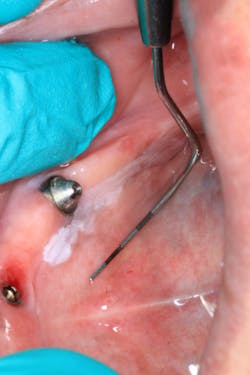

Clinical assessment revealed a white, corrugated lesion lingual to the acrylic of the fixed hybrid prosthesis (figure 2). The lesion measured 5x24 mm and was not able to be scraped off or removed. It was not painful or symptomatic, and no swellings were noted in the sublingual or submandibular lymph node areas (figures 3 and 4).

The unknown etiology of the lesion automatically put it into a category of high-risk leukoplakia, especially since it had just recently manifested and there had been a history of previous biopsy to the area that was diagnosed as precancerous tissue. The patient was seen in my office for prosthesis removal and then referred to an oral surgeon, where she had an excisional biopsy under local anesthesia (figures 5 and 6). The patient's prosthesis was adjusted and appropriate follow-up care was put in place.